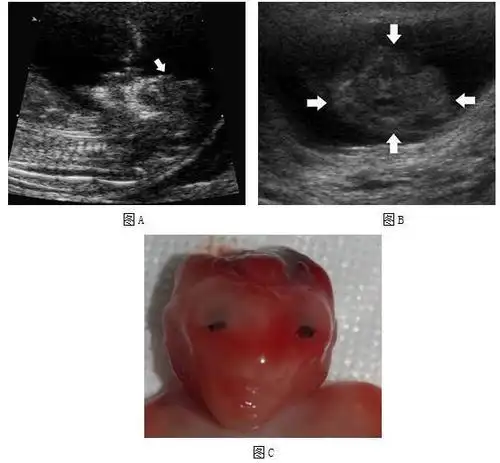

胎儿严重结构畸形的产前筛查与诊断:从中孕期提前到早孕期